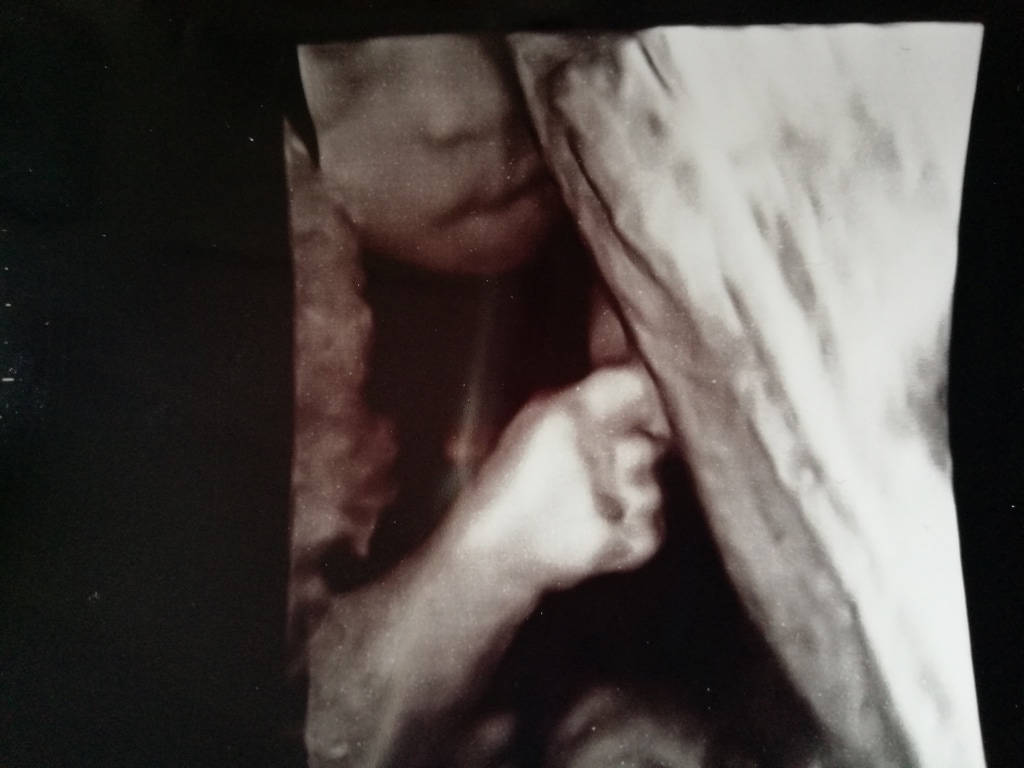

Ik was over de 30 weken zwanger van mijn baby met Trisomie 18

De 30 weken haalde ik gelukkig, Loïs was nog bij ons. We hadden weer een echo in het ziekenhuis en een week later hadden we de vruchtwaterpunctie. Als ze geen chromosoomafwijking zou hebben, zou er gekeken worden naar een eventuele hartoperatie. Ik was erg gespannen voor de punctie en ik voelde me er niet helemaal goed bij. Toch vonden we dat we dit moesten doen, zodat we Loïs een zo goed mogelijke kans konden geven, als ze geen trisomie 18 zou hebben.